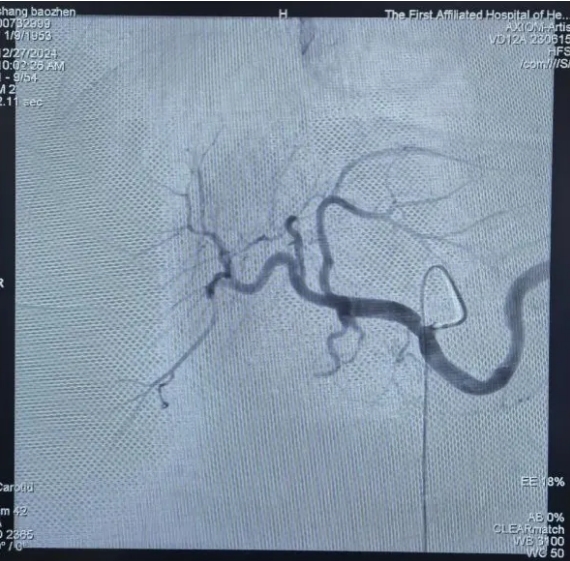

DSA下肝动脉化疗栓塞术:

直击病灶,精准治疗

肝动脉化疗栓塞术(TACE)是一种通过动脉内注射抗癌药物联合栓塞剂的微创治疗手段,常用于治疗肝癌及转移性肝肿瘤。针对患者肝脏多发病变的情况,可采用DSA(数字减影血管造影)引导下的精准治疗方式进行手术。术中,通过局部麻醉穿刺股动脉置入导管,导管末端精确送达肝总动脉,在高压注射器造影下明确肝左叶病灶供血动脉走行,随后将微导管插入肝左动脉,缓慢注入含碘化油的乳化剂,精准封堵病灶供血。术中监测和术后影像均显示碘化油在肝左叶病灶内明显沉积,药物滞留效果良好。为确保疗效、减少副作用,手术采取多次缓慢灌注技术,最终精准阻断肿瘤供血,达到消解病灶的目的。术后,患者恢复良好,未出现明显并发症,目前正在制定后续治疗计划。

腹腔干造影。